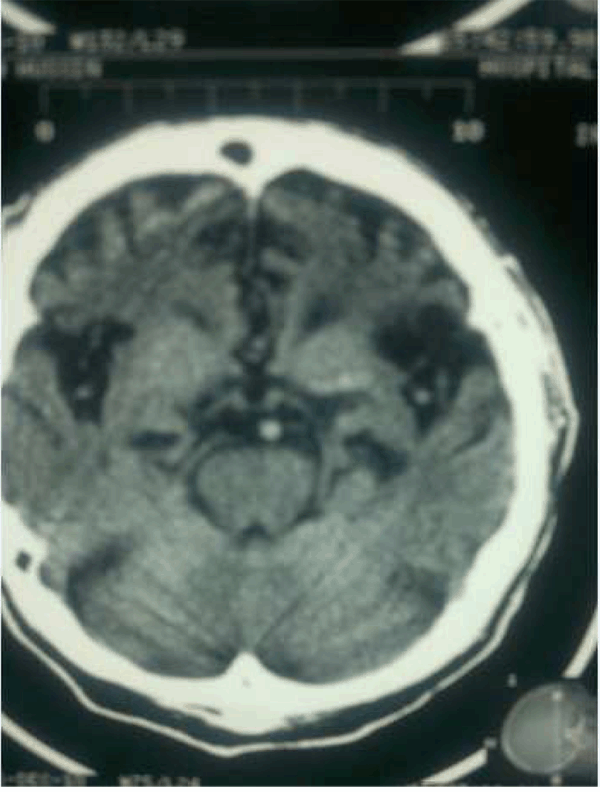

Patient's full blood count, renal functions, thyroid functions, liver functions and routine urine examinations were normal. He tested negative for HIV, Hepatitis B, Hepatitis C, venereal disease research laboratory test (VDRL), and treponema palladium hemagglutination test (TPHA). His serum electrolytes were normal. Based on the history and clinical presentation, a diagnosis of dementia with Herpes simplex of left thigh was considered. Computed tomography scan of the brain showed atrophy of frontal and temporal areas of the brain. (Figure 1) (Figure 2) (Figure 3) (Figure 4)

Figure 2: Bifrontotemporal atrophy and prominent sylvian fissures. Frontal horns of ventricles are clearly visible.

Macroscopic examination of the brain of a patient with FTLD typically shows symmetrical focal atrophy of the frontal lobes, temporal lobes. Microscopic examination of the cerebral cortex in most forms of FTLD, shows microvacuolation and neuronal loss. On staining for deposits in neurons, abnormal tau protein aggregates (46%) and ubiquitin-positive inclusions (29%) were found.[6] Our patient had frontal and temporal lobe atrophy on CT scan. The exact etiology and pathophysiology of frontotemporal dementia is incompletely understood but recent studies suggest that genetics plays an important role in disease causation. [7] This is supported by the fact that about 50% of patients with frontotemporal dementia (FTD) report a positive family history. [7]